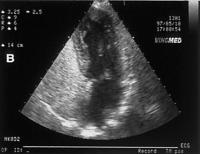

Abbildung 3b: Transthorakale Kontrast-Echokardiographie (apikaler 4-Kammer-Blick) mit dem rechten Vorhof (RA), rechten Ventrikel (RV), linken Vorhof (LA) und linken Ventrikel (LV) eines Patienten mit HPS. (A): Vor der Applikation des Kontrastmittels (geschüttelte Kochsalz-Lösung); (B): Passage der Microbubbles durch den rechten Vorhof und rechten Ventrikel; (C): Sichtbarwerden der Microbubbles im linken Vorhof und linken Ventrikel, 6 Herzschläge nach der Passage durch den rechten Vorhof/rechten Ventrikel.

Keywords: EchokardiographieHepatologieHepatopulmonales SyndromHPS